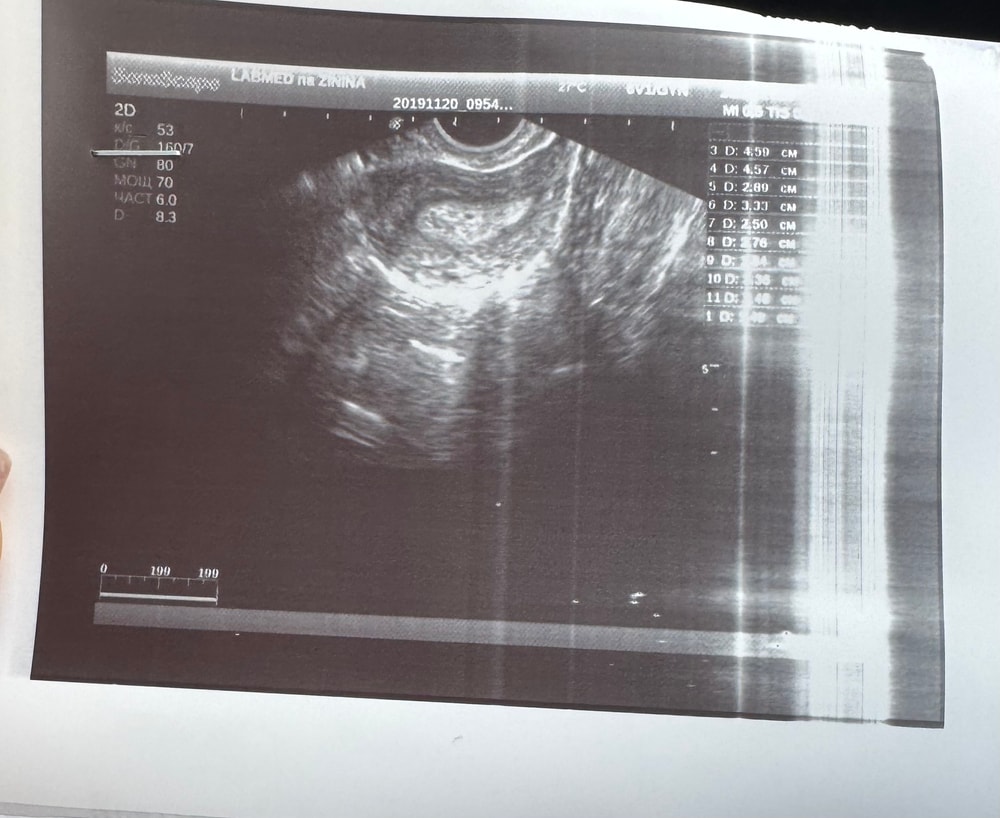

и вопрос все же актуален! ЧТО УЗИСТ УВИДЕЛА НА УЗИ ОТ 20.11? МИОМА, ПОЛИП, КИСТА, ПРИШЕСТВИЕ ХРИСТА???🤨🤨🤨 (на экране показала, и на снимке видно маленькое чёрное образование, о котором она сказала, что вероятно это может являться плодным яйцом, но в заключении ничего не написала). Тогда, с какой стати, ВЫ МЕНЯ ИЗВИНИТЕ, ХГЧ маленький для визуализации, аааа??? Или я не весь Гугл обшарила😛

дублирую снимок узи от 20.11 и результат сегодняшнего ХГЧ. Или всё-таки, когда она увидела «маааааленькое чёрное пятно», оно только имплантировалось? И есть вероятность появления второго? Я что за уникальный случай😡